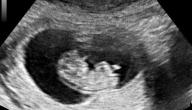

ينمو الجنين ويتطوَّر داخل رحم الأم محاطاً بالسائل الأمينوسي (بالإنجليزية: Amniotic Fluid) الذي يُشبَّه بوسادة تحمي الجنين من الضغط المفرط، وفي حال تمزُّق الألياف الحاملة للسائل الأمينوسي فإنَّ حزماً من الألياف تخرج من الكيس وتلتفُّ حول الجنين مسبِّبة الضغط عليه، ويؤدِّي ذلك إلى الإصابة بمتلازمة الشريط السلوي (بالإنجليزية: Amniotic Band Syndrome) التي تتمثَّل ببتر ذراع أو ساق الجنين، ومن العوامل البيئيَّة الأخرى التي قد تسبِّب تشوُّهات الجنين هي عدم كفاية كميَّة السائل الأمينوسي، إذ يتسبَّب ذلك بوقوع ضغط إضافي على الجنين مسبِّباً نقص تنسُّج الرئة (بالإنجليزية: Pulmonary Hypoplasia)، والذي يتمثَّل بنقص في نموِّ وتطوُّر الرئتين.[٧]